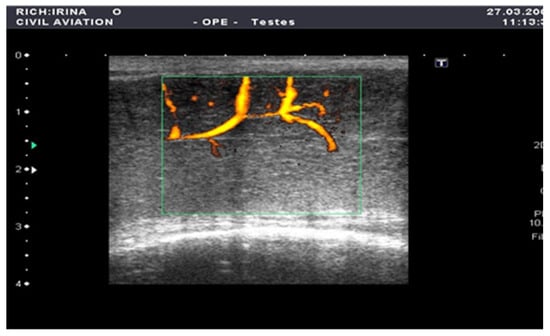

Figure 2.

Penile CDUS during pharmacologically induced erection. Signs of arterial insufficiency: visualization of arterial stenosis areas, with spiral arteries showing uneven and asymmetric contrast enhancement.